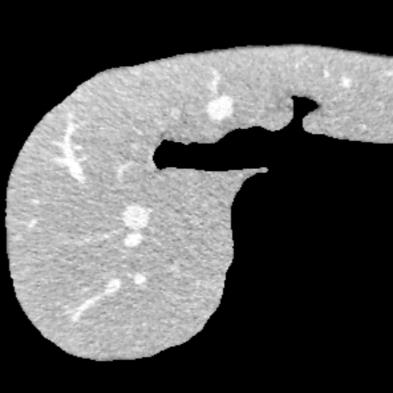

Manually segmenting the hepatic vessels from Computer Tomography (CT) is far more expertise-demanding and laborious than other structures due to the low-contrast and complex morphology of vessels, resulting in the extreme lack of high-quality labeled data. Without sufficient high-quality annotations, the usual data-driven learning-based approaches struggle with deficient training. On the other hand, directly introducing additional data with low-quality annotations may confuse the network, leading to undesirable performance degradation. To address this issue, we propose a novel mean-teacher-assisted confident learning framework to robustly exploit the noisy labeled data for the challenging hepatic vessel segmentation task. Specifically, with the adapted confident learning assisted by a third party, i.e., the weight-averaged teacher model, the noisy labels in the additional low-quality dataset can be transformed from "encumbrance" to "treasure" via progressive pixel-wise soft-correction, thus providing productive guidance. Extensive experiments using two public datasets demonstrate the superiority of the proposed framework as well as the effectiveness of each component.

翻译:将来自计算机地形学(CT)的肝脏船只人工分割,由于船只的低调和复杂形态,由于低调和复杂的形态,造成极端缺乏高质量的标签数据,因此比其他结构更需要专门知识和难度大得多。如果没有足够的高质量的说明,通常的数据驱动的基于学习的方法就会与不足的培训斗争。另一方面,直接引进低质量说明的额外数据可能会混淆网络,导致不良的性能退化。为了解决这一问题,我们提议建立一个新的、由教师协助的、有说服力的、有说服力的学习框架,为具有挑战性的肝脏船只分解任务强有力地利用响亮的标签数据。具体地说,在第三方(即加权平均教师模式)的协助下,经过变通的自信学习后,额外低质量数据集中的噪音标签可以从“阻力”转变为“压力”,通过渐进式的像素方法的软校正,从而提供富有成效的指导。使用两个公共数据集进行的广泛实验,显示了拟议框架的优越性以及每个组成部分的效能。